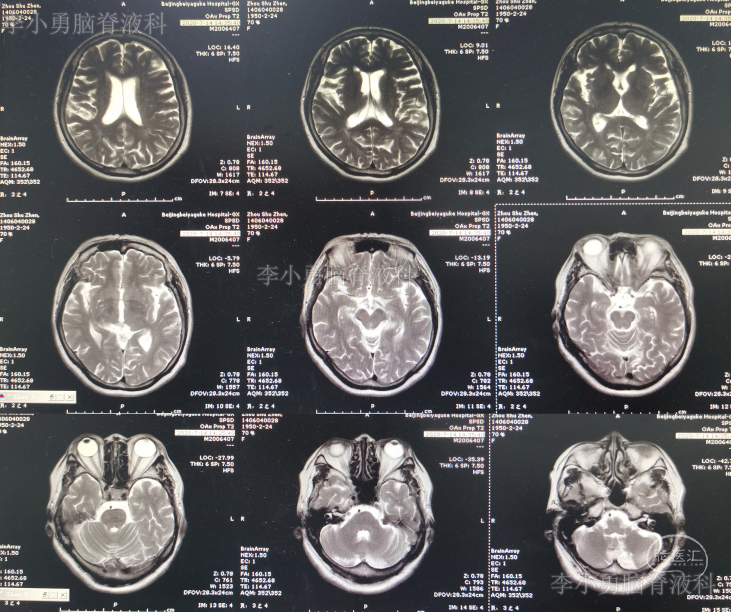

2020年5月10日(即第一次颈椎术后18天)患者洗脸时再次突发头晕,表现为天旋地转,恶心,呕吐视物旋转,行走不稳,经休息症状不缓解,再次就诊入院。查头颅MR显示急性小脑梗塞(图-3),给予改善微循环、降血脂、控制血压及对症治疗后患者头晕好转出院,但行走时仍有摇晃感。

图-3:2020年5月10日头颅MR

2020年7月14日(即第一次颈椎病术后83天)患者又出现头晕加重,尤以低头扭头时明显(注:患者未按照医嘱佩戴颈托),而且双上肢放射痛,麻木再次出现,双下肢无力,行走不稳,门诊复查头颅MR示小脑陈旧性梗塞(图-4)。

图-4:2020年7月14日头颅MR